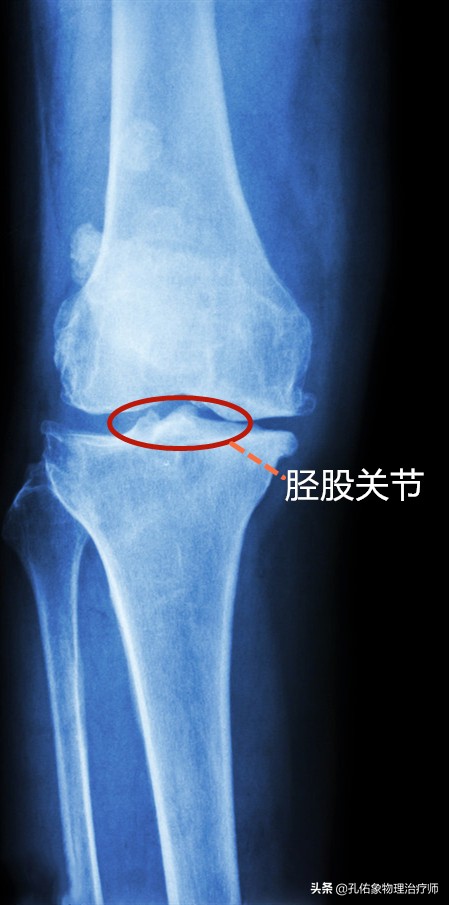

构成人体膝关节复合体之一的关节,就是上图所示的大腿骨与小腿骨连接的胫股关节,若是拍片后,它是长这样的,看下图:

X片胫股关节